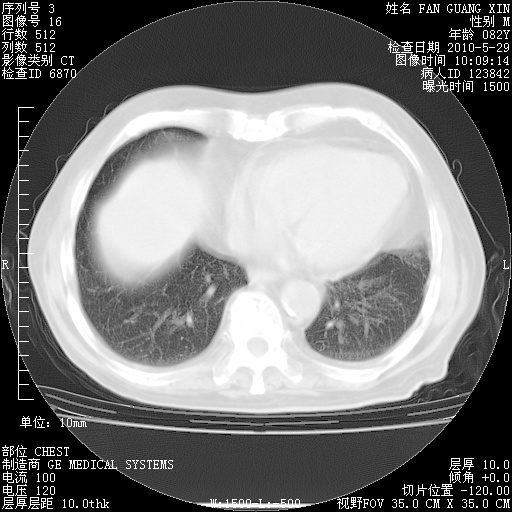

还需要哪些辅助检查?我们医院排除真菌感染没有任何检验方法,胸片好像能够排除肺部真菌感染。

明天复查血常规、血生化? |